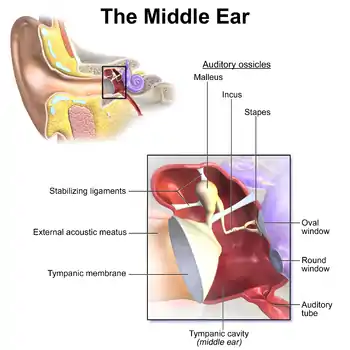

Middle ear

The middle ear lies between the outer ear and the inner ear. It consists of an air-filled cavity called the tympanic cavity and includes the three ossicles and their attaching ligaments; the auditory tube; and the round and oval windows. The ossicles are three small bones that function together to receive, amplify, and transmit the sound from the eardrum to the inner ear. The ossicles are the malleus (hammer), incus (anvil), and the stapes (stirrup). The stapes is the smallest named bone in the body. The middle ear also connects to the upper throat at the nasopharynx via the pharyngeal opening of the Eustachian tube.[7][11]

The three ossicles transmit sound from the outer ear to the inner ear. The malleus receives vibrations from sound pressure on the eardrum, where it is connected at its longest part (the manubrium or handle) by a ligament. It transmits vibrations to the incus, which in turn transmits the vibrations to the small stapes bone. The wide base of the stapes rests on the oval window. As the stapes vibrates, vibrations are transmitted through the oval window, causing movement of fluid within the cochlea.[7]

The round window allows for the fluid within the inner ear to move. As the stapes pushes the secondary tympanic membrane, fluid in the inner ear moves and pushes the membrane of the round window out by a corresponding amount into the middle ear. The ossicles help amplify sound waves by nearly 15–20 times.[6]